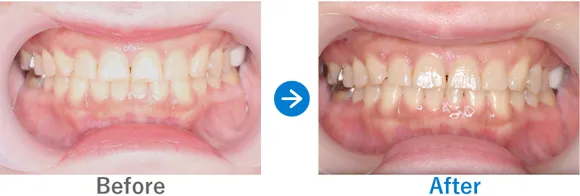

Case4

歯科恐怖症でもセデーションで眠っている間に手術が終了

12年前に治療した左下6が悪化し抜歯予定

インプラント1本:左下6、抜歯テルプラグ

440,000円(内訳:抜歯テルプラグ、インプラント1本(ストローマン)、ガイド、仮歯、セデーション、保証20年)

来院の背景

12年前に他院で治療済みの歯が、10年以上定期検診に通院していたにもかかわらず悪化。抜歯とインプラントを提案されましたが、価格が高かったためセカンドオピニオンで来院されました。

治療結果

抜歯からインプラント1本を無事に終えました。歯科への恐怖心に加え嘔吐反射(歯磨きなどをする際にオエっとなること)もあるため、インプラント手術の際はセデーション(静脈内鎮静法)をし、患者様の不安を取り除いた状態で施術を受けていただきました。

嘔吐反射により歯磨きが十分ではない様子だったので、電動音波歯ブラシをご購入いただき、歯みがき指導を行いました。また、喫煙されておりインプラント周囲炎のリスクが高いため、今後のメンテナンスが重要となります。